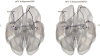

Results: Lower rsFC between the left insula and the left mid-dorsolateral prefrontal cortex and between bilateral insula and right frontopolar prefrontal cortex (FPPFC) was observed in BD compared to MDD and HC. These results were driven by the dorsal anterior and posterior insula (PI). Lower rsFC between the right amygdala and the left anterior hippocampus was observed in MDD compared to BD and HC. These results were driven by the centromedial and laterobasal amygdala. Left PI/right FPPC rsFC showed 78% accuracy differentiating BD and MDD.